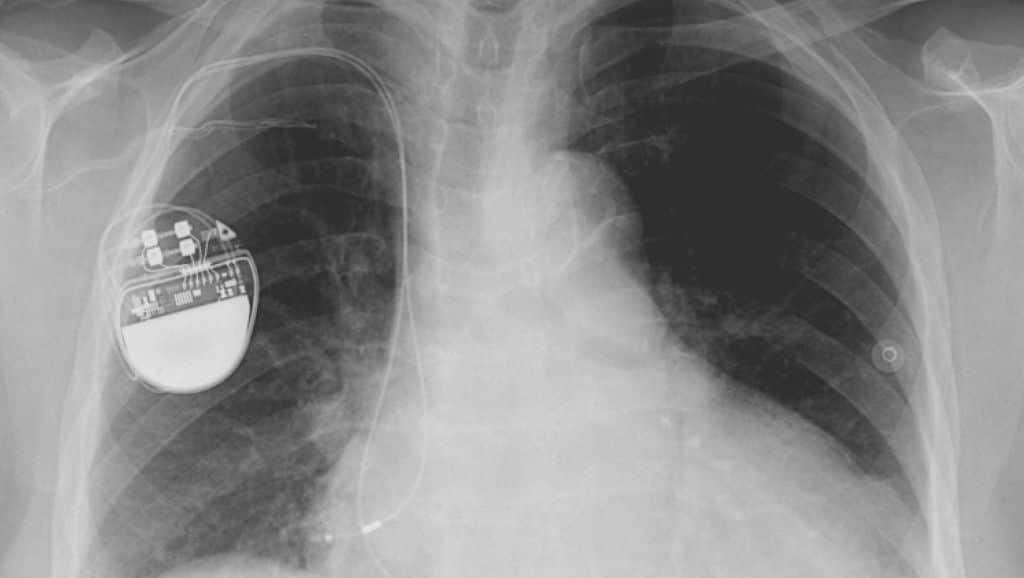

Medtronic makes devices to help control diabetes, manage chronic pain and alleviate Parkinson's disease, and has invented a wireless pacemaker the size of a vitamin pill.